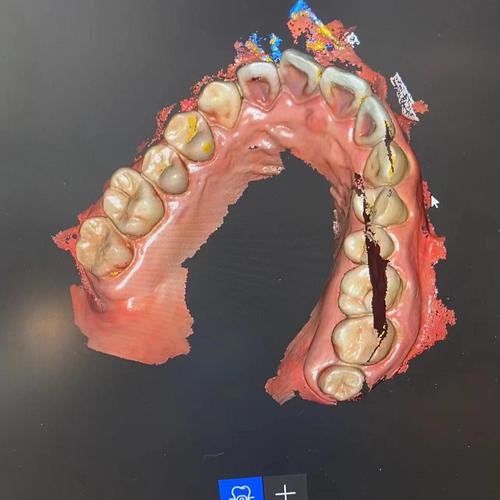

MRCPOP的治疗流程需严格遵循“评估-定制-训练-巩固”的原则,由专业正畸医生进行全面的口腔检查,包括肌功能评估(如舌位、唇肌张力、呼吸模式)、牙列检查及面部发育分析,判断是否存在肌功能异常及错颌风险,若符合适应症,会取模或通过口扫获取口腔数据,定制个性化矫治器,治疗初期,患儿需每日佩戴矫治器2-4小时(同时夜间睡眠时佩戴),配合简单的肌功能训练动作(如舌顶上颚、唇肌抗阻训练等),医生会每4-6周复诊一次,根据训练进展调整矫治器或训练方案,通常治疗周期为6-12个月,待肌功能习惯纠正、颌骨发育改善后,可能配合固定矫治器进一步调整牙齿排列,最后通过保持器巩固效果。